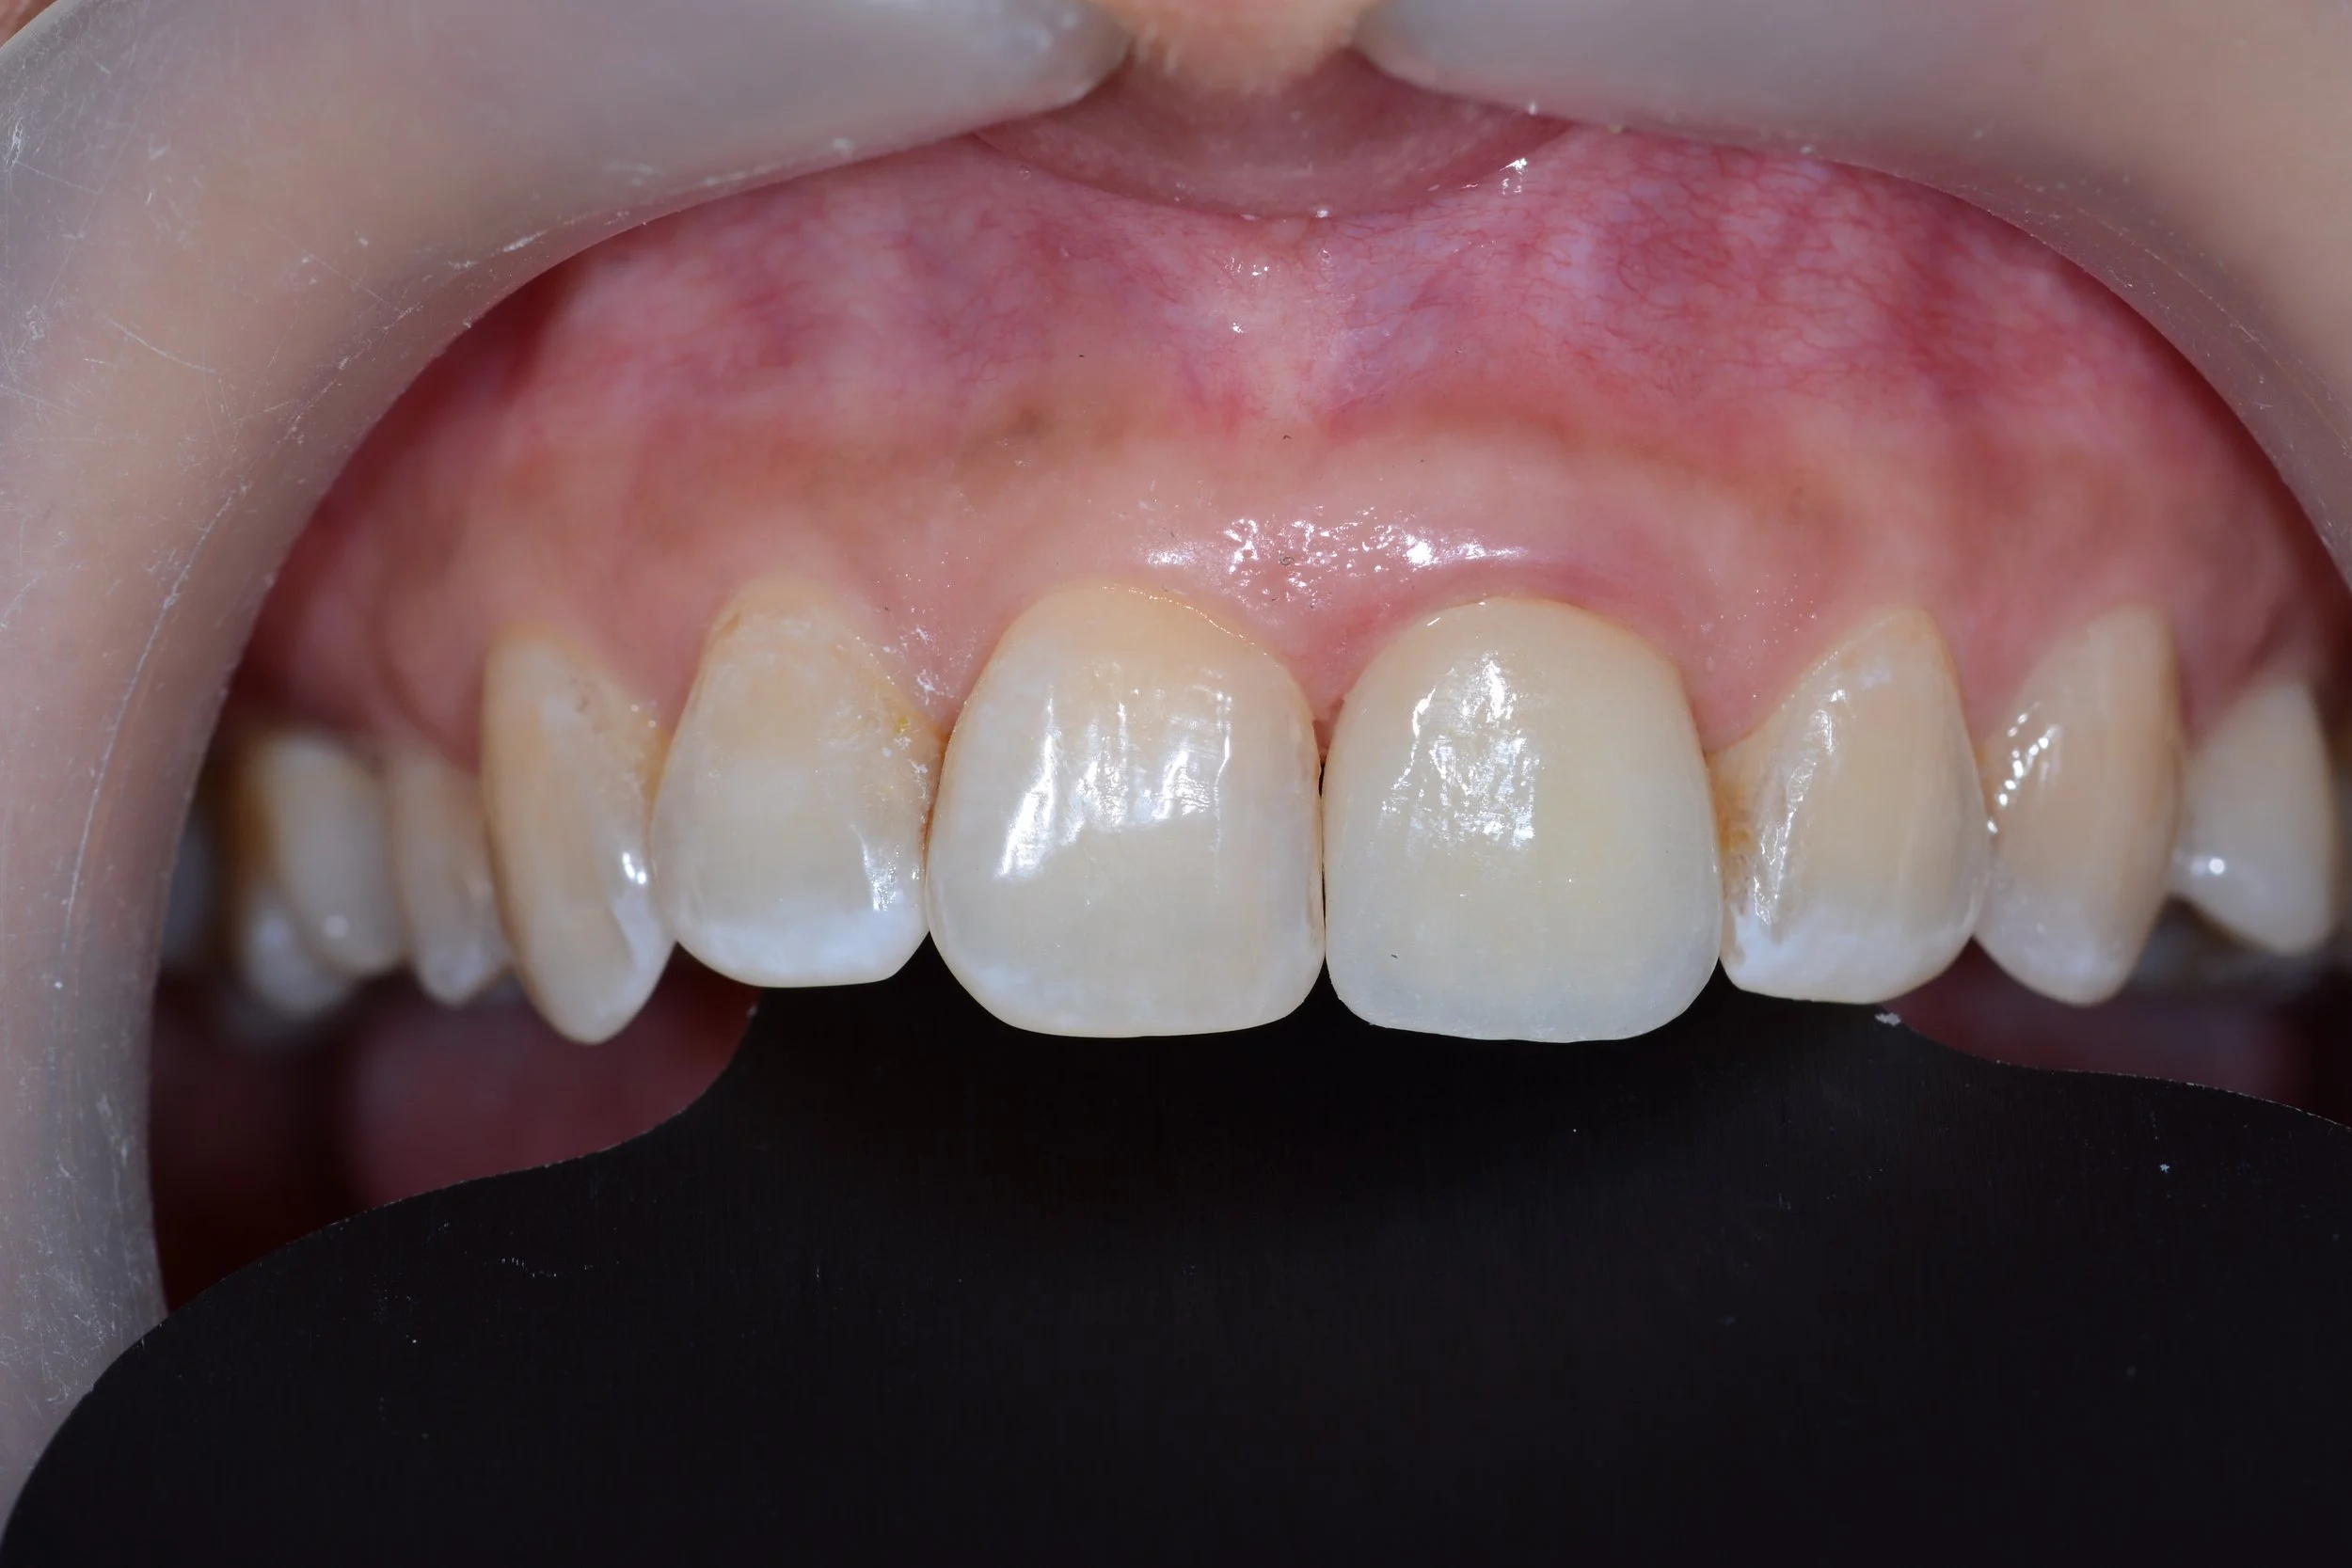

Jason Ho Issue implant-crown.jpg

Replacement with a dental implant and full ceramic crown